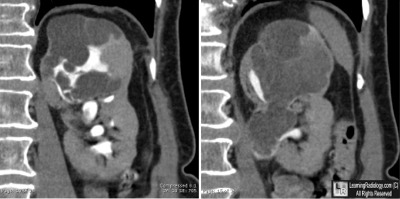

Left Kidney-Contrast-Enhanced CT Urogram

Additional Image - Axial contrast-enhanced CT of the upper abdomen

Additional Images

Axial contrast-enhanced CT of the upper abdomen

4. Cystic Nephroma

Cystic Nephroma

• Rare, unilateral multi-loculated cystic tumor lacking blastemal elements

• Solitary, well-circumscribed

• Non-communicating fluid-filled locules, surrounded by thick, fibrous capsule

• Do not connect to the collecting system

• Usually quite large (mean 7.6 cm by 9.7 cm)

• Most common in lower pole